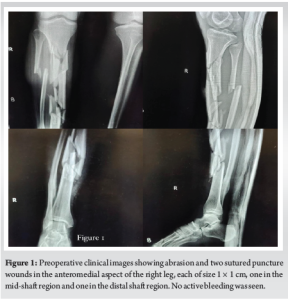

A 27-year-old male presented to the casualty with an open injury of his right leg following a traumatic fall from a motorcycle. On local examination, he had an abrasion and two puncture wounds of size 1 × 1 cm at the anteromedial aspect of the middle shaft and distal shaft of his right leg (Fig. 1) . No active bleeding or symptoms of compartment syndrome were found. The knee and ankle range of motions was painful with the absence of any distal neurovascular deficit. There were no other associated trauma. Pre-operative anteroposterior and lateral radiographs revealed a displaced and comminuted fracture of the shaft of the tibia and fibula (Fig. 2). The fracture was provisionally stabilized by an above-knee slab. Routine blood reports were normal.